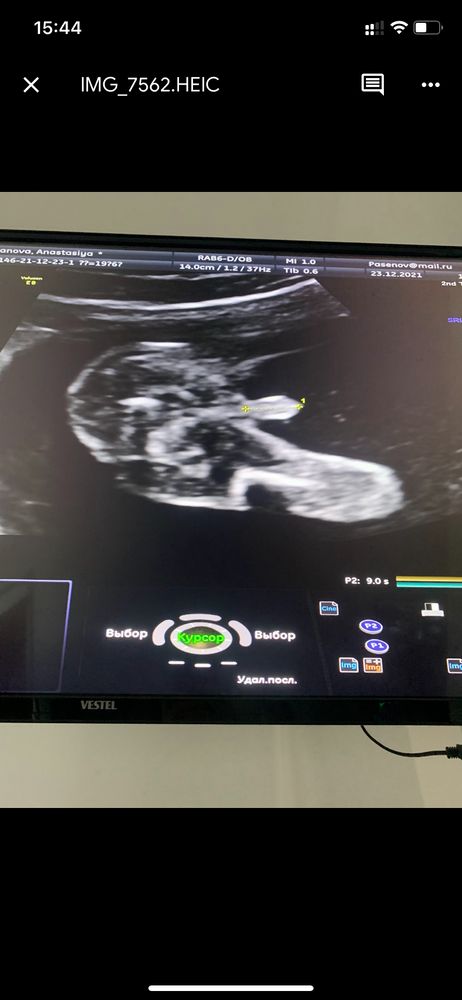

Девочки, привет! Как думаете может быть такой большой писюн в 20 недель 🤣или это пуповина ?

Нормальный) да и возможно не писюн это, а мошонка. Писюн там обычно 1-2 см вроде как🤣

вот наш в 20.0 😄😄

Мне кажется пуповина, так как яичек не видно. 🤷♀️ Но может быть я ошибаюсь.